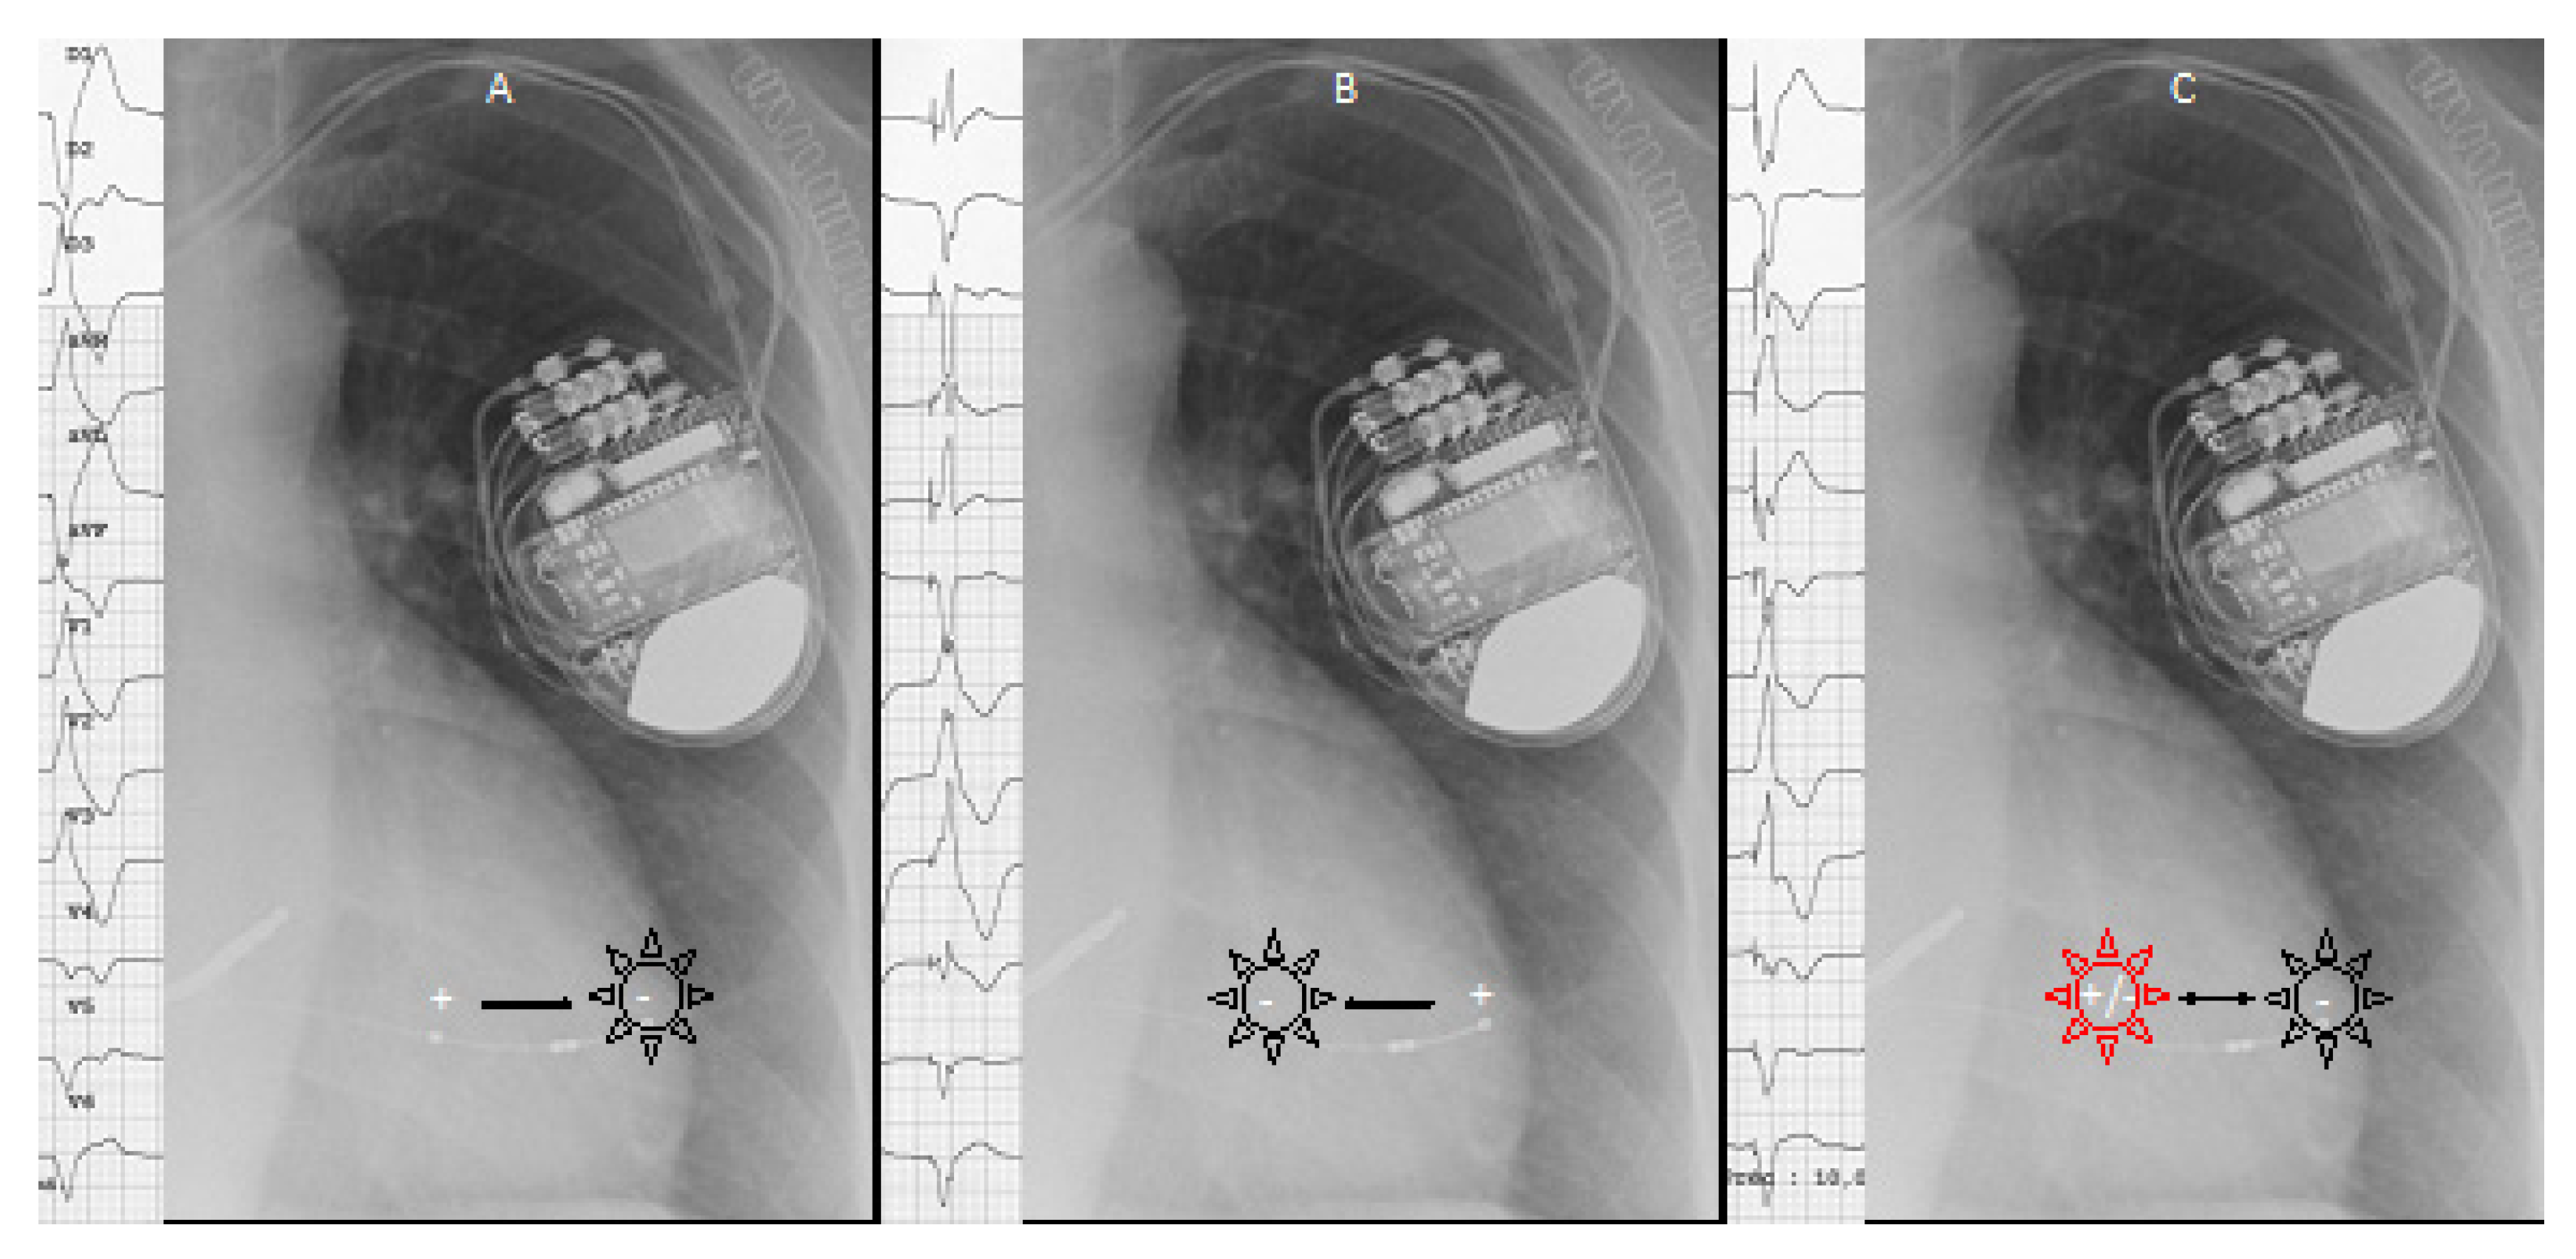

- Morishima, I.; Tomomatsu, T.; Morita, Y.; Tsuboi, H. Intentional Anodal Capture of a Left Ventricular Quadripolar Lead Enhances Resynchronization Equally with Multipoint Pacing. HeartRhythm Case Rep. 2015, 1, 386–388. [Google Scholar] [CrossRef] [Green Version]

- Occhetta, E.; Dell’Era, G.; Giubertoni, A.; Magnani, A.; Rametta, F.; Blandino, A.; Magnano, V.; Malacrida, M.; Marino, P. Occurrence of Simultaneous Cathodal-Anodal Capture with Left Ventricular Quadripolar Leads for Cardiac Resynchronization Therapy: An Electrocardiogram Evaluation. EP Europace 2016, 19, 596–601. [Google Scholar] [CrossRef]

- Dell’Era, G.; De Vecchi, F.; Prenna, E.; Devecchi, C.; Degiovanni, A.; Malacrida, M.; Magnani, A.; Occhetta, E.; Marino, P. Feasibility of Cathodic-Anodal Left Ventricular Stimulation for Alternative Multisite Pacing. Pacing Clin. Electrophysiol. PACE 2018, 41, 597–602. [Google Scholar] [CrossRef]